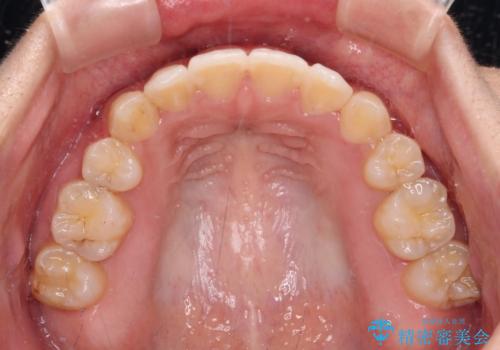

著しい八重歯が気になる インビザラインでの矯正治療

- 顕著な八重歯が気になるとのことで来院された患者様です。

インビザラインでの治療を希望されましたが、インビザライン単独では困難と判断されたため、補助装置や一部ワイヤー装置を用いて行うこととしました。

叢生が強いため、上下左右第一小臼歯4本を抜歯することとしました。